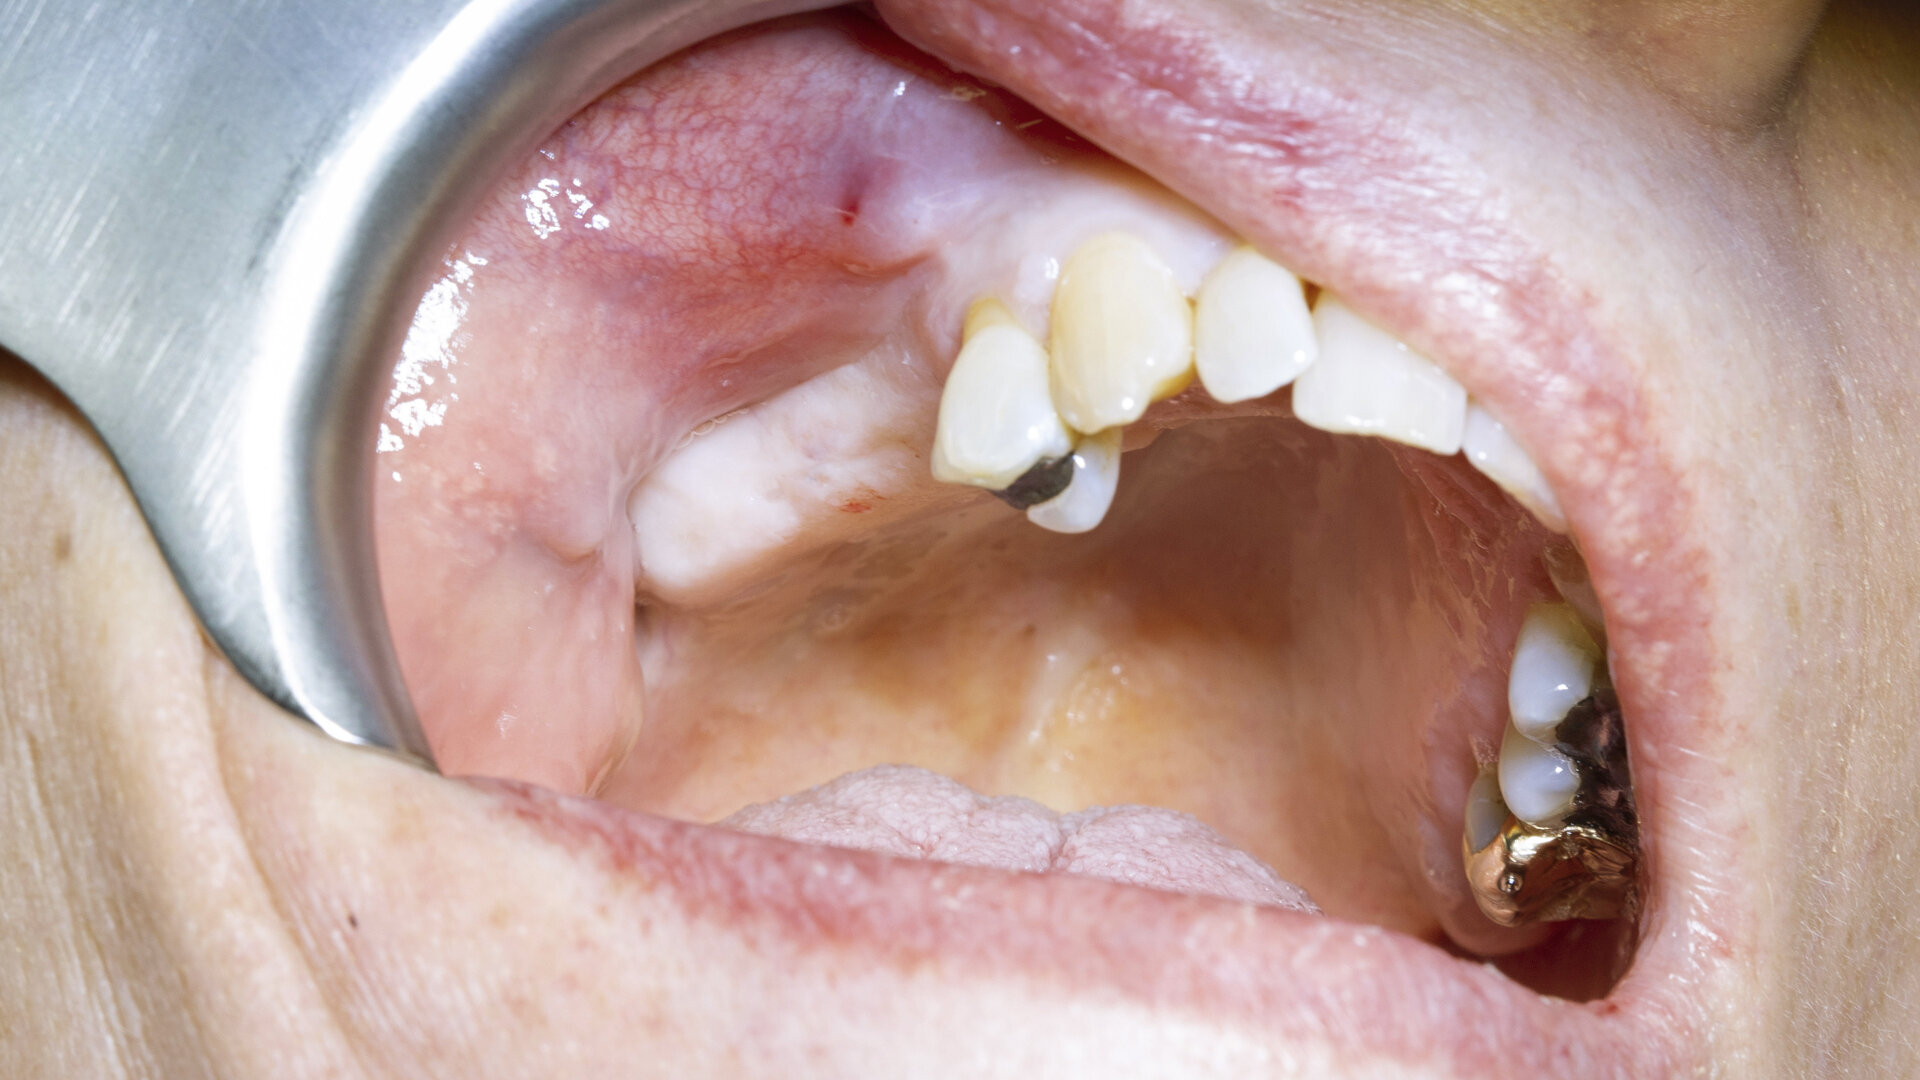

A 64-year-old female patient presented to our practice with a heavily restored dentition. Her failing maxillary right first molar and second premolar had been extracted by her general dental practitioner (Fig. 1), leaving an unbounded edentulous area. Radiographic assessment indicated that there was ample bone depth in the posterior maxilla to allow for satisfactory implant placement (Fig. 2). An implant solution was provided using two individual screw-retained crowns supported by two OmniTaper EV implants (Dentsply Sirona) and using a digital workflow with Primescan and Atlantis (Dentsply Sirona).